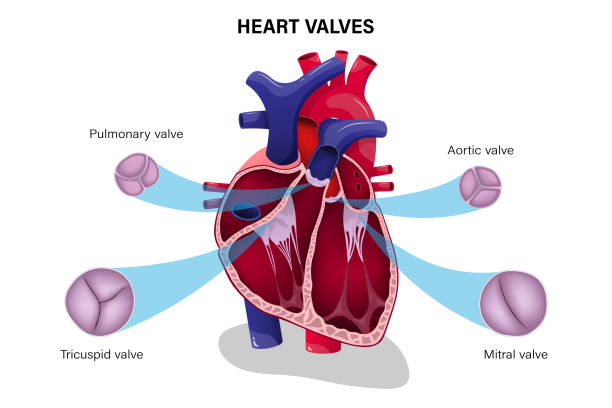

Valve Surgery

The heart’s valves play a vital role in controlling blood flow. When valves do not open or close properly, it can lead to serious health complications such as shortness of breath, fatigue, and chest pain. Valve surgery focuses on repairing or replacing these faulty valves to restore normal heart function. Dr. Pokharna specializes in both valve repair and replacement procedures, using advanced technology to provide long-term results. His expertise ensures improved quality of life for patients with valve disorders.